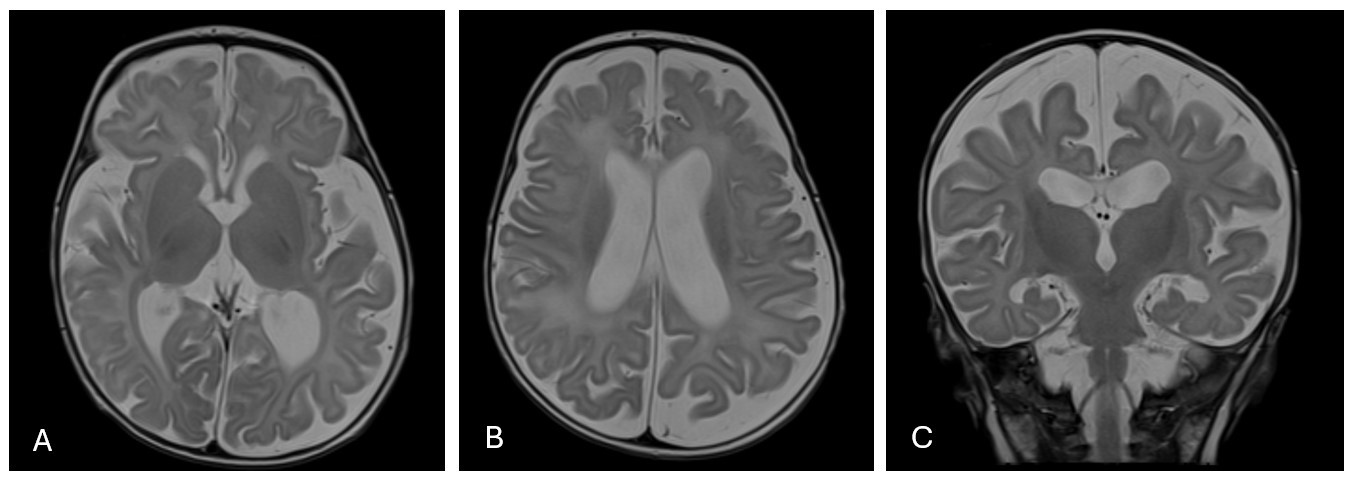

Results: The first brain MRI was performed on a 2-month-old infant who was hospitalized following a rapid progression of HC. The brain MRI revealed diffuse enlargement of the subarachnoid space and all ventricles, with normal brain parenchyma and no abnormal signal in white or grey matter. No evidence of brain atrophy or prior hemorrhage was observed (Figure 1).

MRI brain T2 image of a 2-month-old NLE infant with rapid progression of head circumference.

Axial T2 images (A & B) and coronal T2 images (C) demonstrated diffuse enlargement of subarachnoid space and ventricles. Normal signal of grey and white matter.